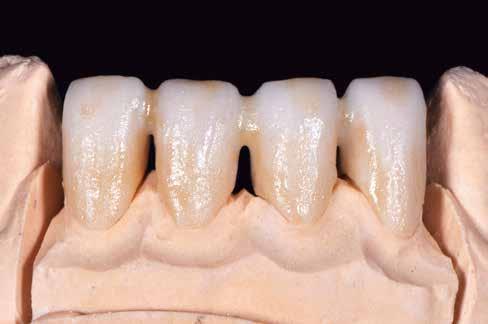

A kezelések második fázisában a pácienssel közösen non-prep/ minimálinvazív héjak készítése mellett döntöttünk (6. és 7. ábra).

Az ilyen jellegű ellátás során csupán a lehető legkisebb mennyiségű foganyag kerül eltávolításra. A minimálinvazív beavatkozás elvégzését lehetővé tevő feltételeket a fogszabályzó kezelés során alakítottuk ki. A fogazat minimálinvazív módon készített héjakkal történő ellátásához a fogaknak olyan pozícióban kell lenniük, amely lehetővé teszi az esztétikai megjelenés additív eljárások alkalmazása mellett történő optimalizálását. Azonban az ellátás során előbbiekben felsoroltakon kívül más szempontokat is figyelembe kell vennünk. Amennyiben a páciens a jelenleg látható fogszínéhez képest jelentős változást szeretne elérni, úgy sokkal vastagabb héjak készítésére van szükség, és az ezáltal megnövekedett helyigény miatt sok esetben nincs lehetőség kizárólag additív eljárások alkalmazására (8. ábra). Mivel a cikkben bemutatásra kerülő eset ellátása során a fogazat helyzeti rendellenességei az előzetes orthodonciai kezelés keretei között korrekcióra kerültek, ezért lehetőségünk adódott a restauratív fázis minimálinvazív módon történő elvégzésére. Az általunk alkalmazott terápia hátrányai között szerepelt, hogy az elvégzett beavatkozások időigénye miatt a tervezett végeredményt csupán viszonylag hosszú idő után tudtuk elérni.

A páciens teljesen elégedett volt a kezelések befejezését követően elért esztétikai végeredménnyel (9. ábra). A terápiás erőfeszítéseink eredményeinek köszönhetően újra képes felszabadultan nevetni és mosolyogni. A cikkben bemutatásra kerülő eset jól példázza a multidiszciplináris beavatkozások alkalmazásában rejlő előnyöket. A megfelelő sorrendben végzett orthodonciai és restauratív kezelésekkel lehetővé vált a páciens mosolyának minimálinvazív módszerekkel történő optimalizálása. A körültekintő tervezésnek köszönhetően nem került sor felesleges beavatkozások elvégzésére, és emiatt a kezelések befejezéséhez szükséges idő sem nyúlt a szükségesnél hosszabbra. Arra is felhívnánk a figyelmet, hogy a jól megszervezett, továbbá a lehető legkevesebb rendelési időt felhasználó kezelések – a beavatkozásokat végző fogorvosok számára is – rendkívül kedvezőek lehetnek.